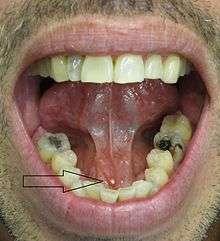

- Palpable hard lump, if the stone is located near the end of the duct.[1][3] If the stone is near the submandibular duct orifice, the lump may be felt under the tongue.

- Erythema (redness) of the floor of the mouth (infection).[3]

- Pus discharging from the duct (infection).[3]